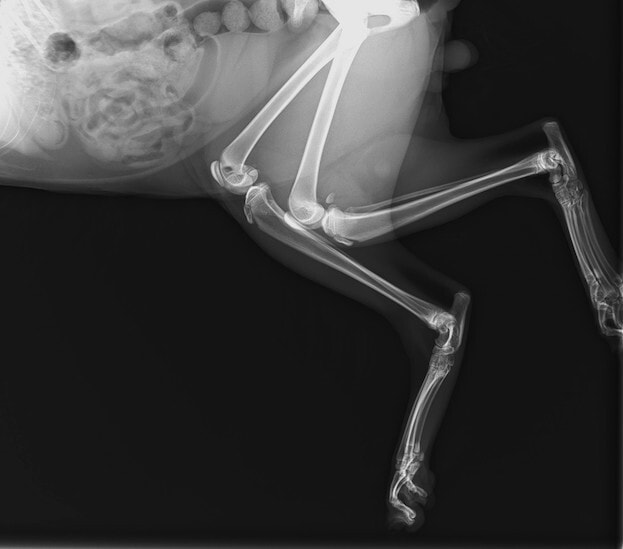

症例:交通事故による椎体脱臼

柴犬:9歳、避妊雌

交通事故直後、胸腰部に激しい疼痛、両後肢に完全麻痺を認め、シェフシェリントン徴候を呈していました。レントゲン検査において、第11-12胸椎間の脱臼が認められました。

脊髄の減圧、脊柱管の再構築・安定化を目的に、片側椎弓切除術およびMatrixMANDIBLE Plateによる椎体固定を実施しました。

隣接椎体を架橋するようにプレートを設置しました。

術後レントゲン写真